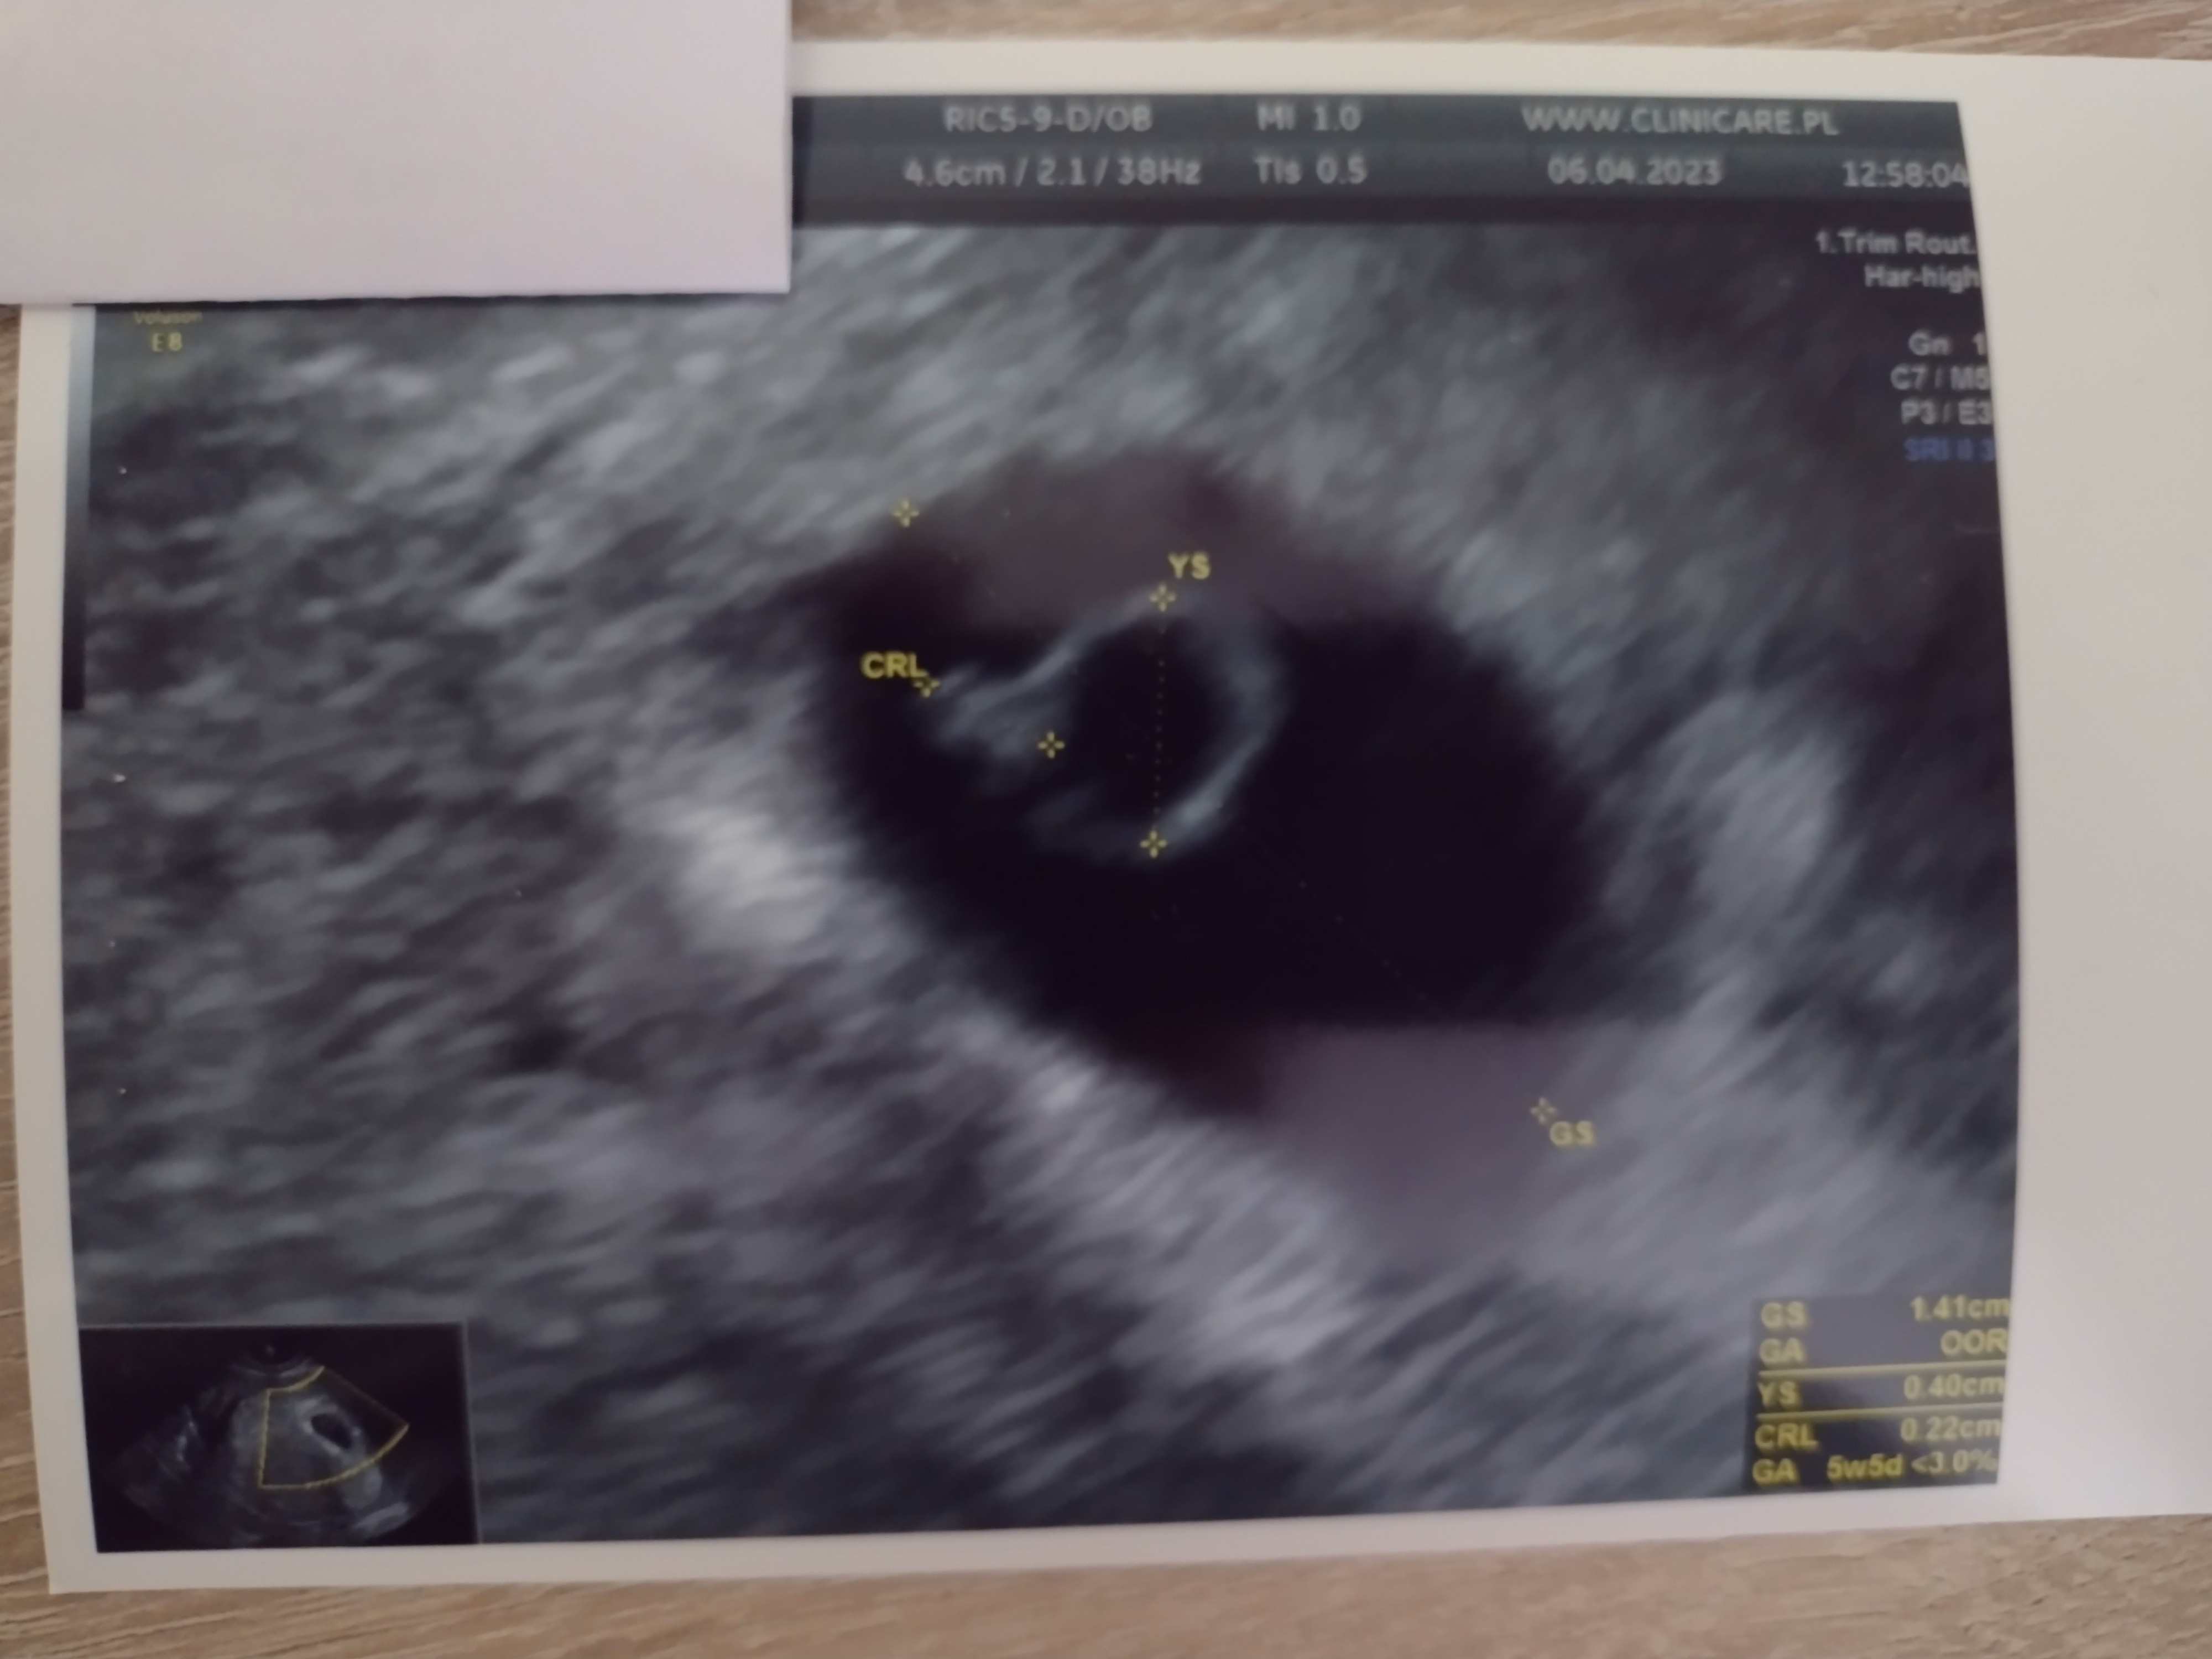

Jestem już po wizycie. 2mm szczęścia z bijącym serduszkiem ❤️ kolejna wizyta 20.04. jestem już na L4.

Załączniki

• IMG_20230406_144443290.jpg

IMG_20230406_144443290.jpg

834,3 KB · Wyświetleń: 159